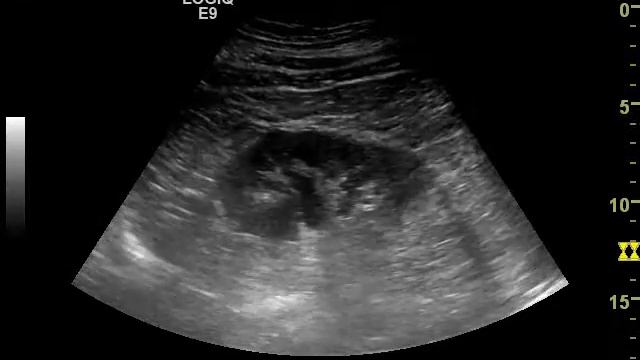

Кисты левого почечного синуса